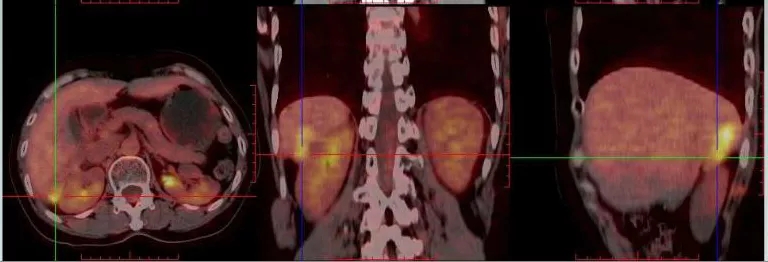

2021.5.8 PET-CT:肝肾隐窝转移灶。2021.5.12复查CA125水平为95.5U/ml。

PET-CT检查结果